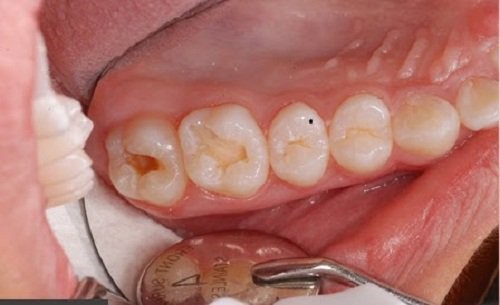

Răng sâu đến tuỷ

Khi bị sâu răng chạm đến tủy, bạn có thể phải điều trị tủy răng